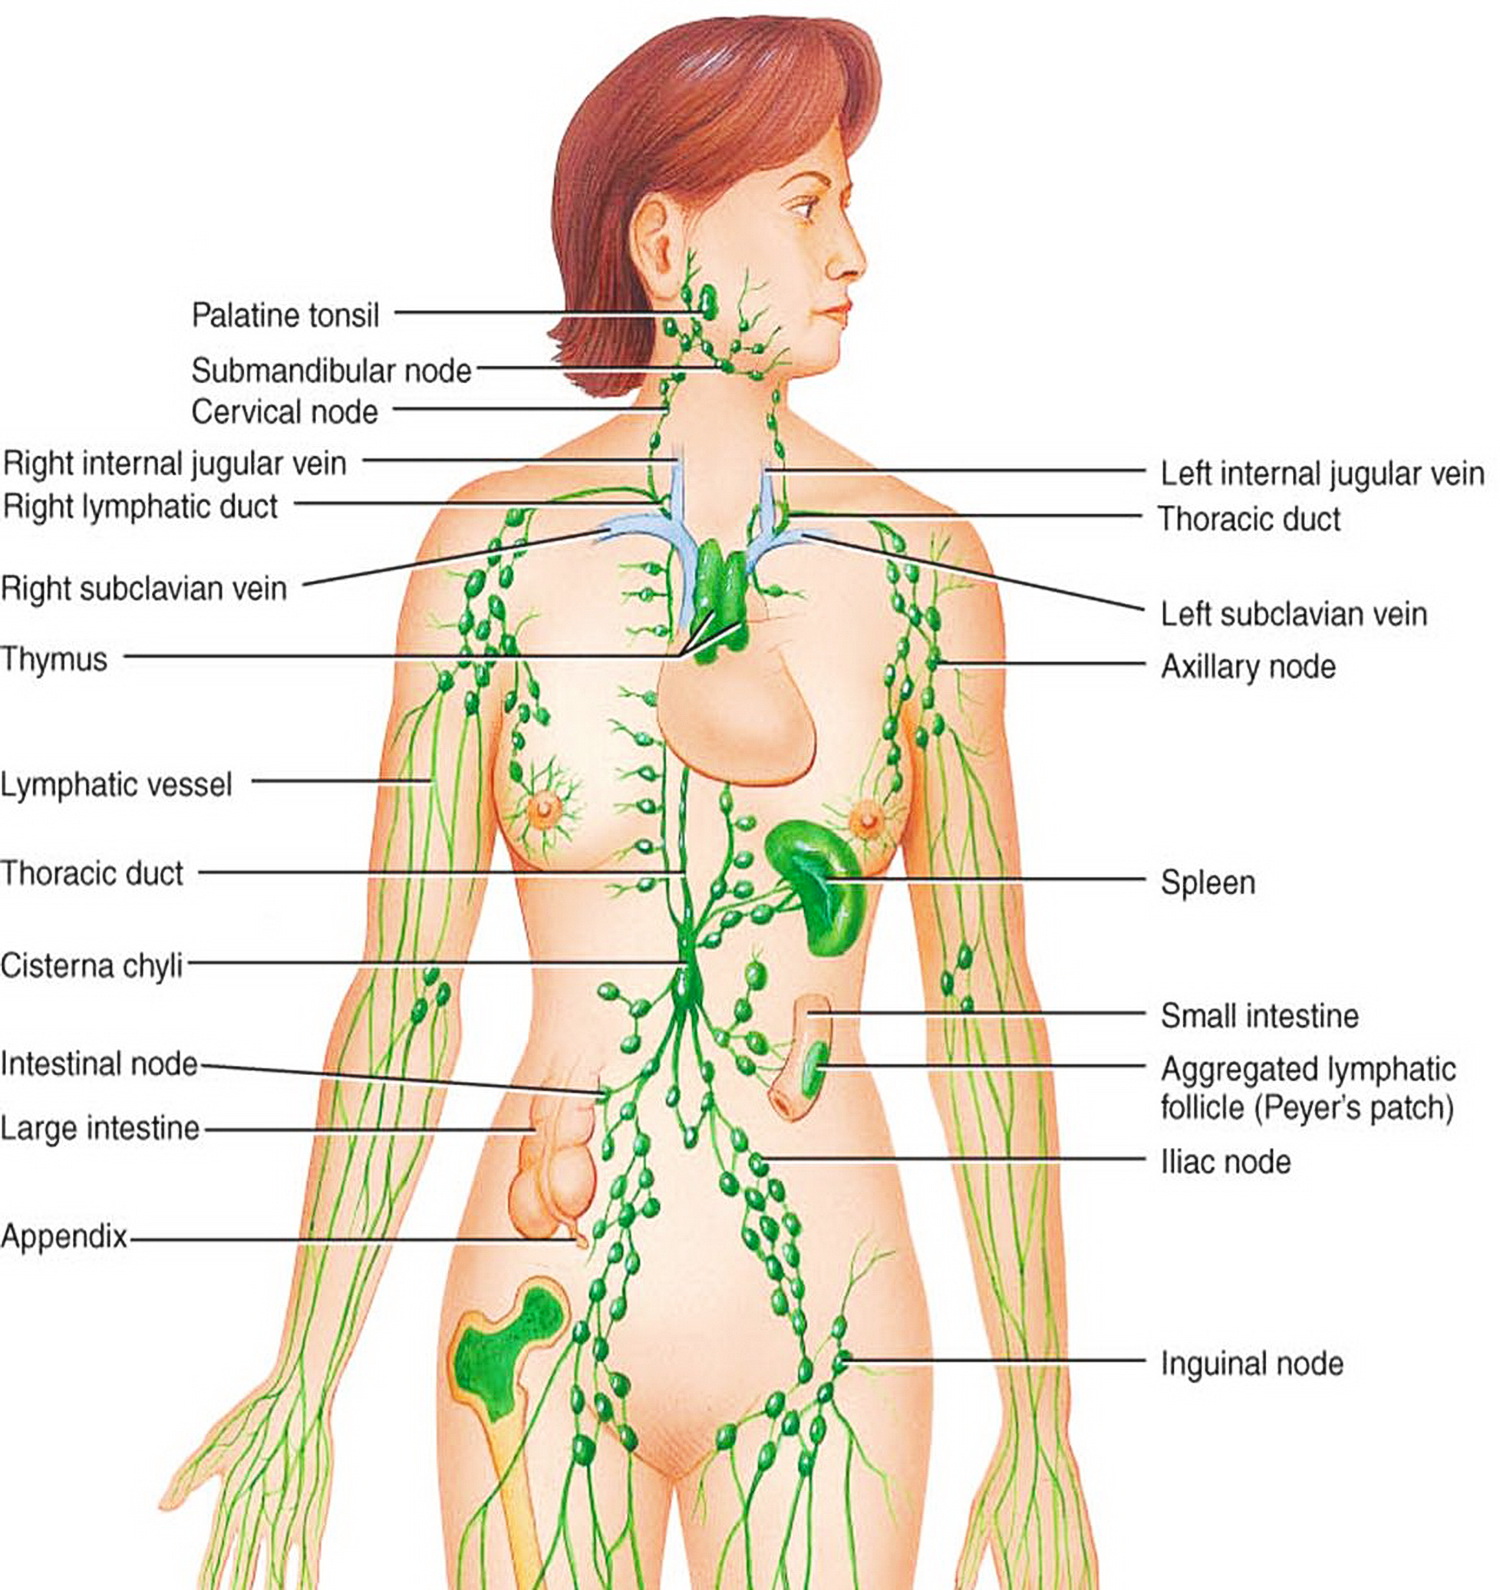

Изображения и схемы: как выглядит лимфа